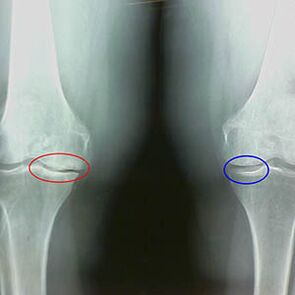

Determining the degree of arthrosis occurs by X -Rayto detect the participation in the pathological process of bone structures.Their change indicates that the muscle system is an imbalance within 5-10 years.As a rule, peoplePain hurts for several years.

Features of the second stage of early X -Rey Artrosis:

- Inter-Russian Tubercles in Tibia, which is closed;

- to narrow the joint gap on the medial side;

- The remote edges of the air conditioners on the medial parties depending on the development of the less lateral, valgus or different joint deformation.

For the second stage in LarsenThe contraction of more than 50% of the joint cavity is characteristicBut it can only be compared with a dynamics or different playful.